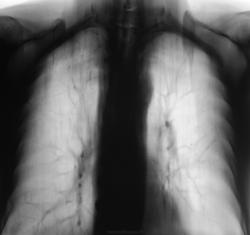

Есть изменения в обеих верхушках.

На верхушках какие-то изменения тоже вижу. Не могу понять кальцинаты ли в внутригрудных лимфоузлах? и Что с левой ключицей на 2-м снимке?

И на первом, и на втором снимках консолидированный перелом левой ключицы, правда слослось не лучшим образом, с деформацией...